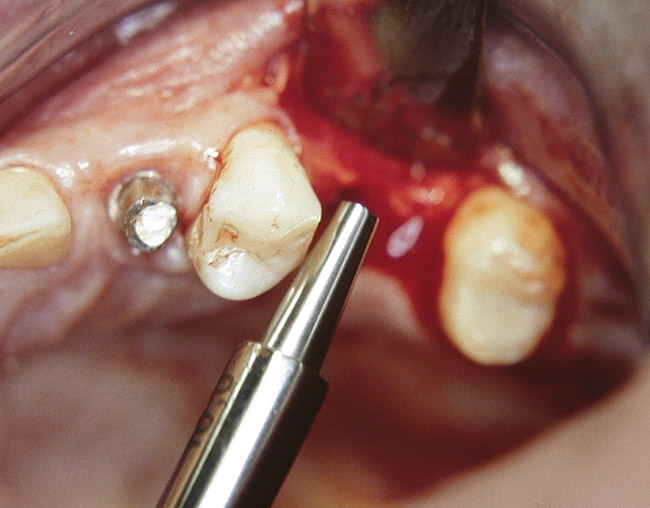

At the time of surgery, the tooth was extracted without harvesting any mucosal flap because the implant site was prepared by means of a pilot drill bur (Figure 13) and alternating osteotomes (Figure 14A and Figure 14B). The implant was positioned and showed primary stability. The implant was loaded 2 days after surgery. Then, splinted PFM crowns supported by custom gold abutments were delivered. At 6 months posttreatment, the radiograph revealed no bone resorption and the clinical result was optimal (Figure 15A and Figure 15B).

Figure 14A and Figure 14B Alternating osteotomes were used to prepare the implant site.

Figure 14a  Alternating osteotomes were used to prepare the implant site.

Figure 14a

Figure 14b  Alternating osteotomes were used to prepare the implant site.

Figure 14b